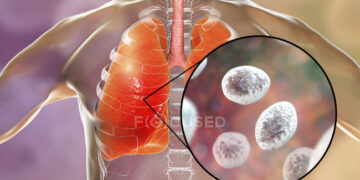

হার্টবিট ডেস্ক ফুসফুস আমাদের শরীরের গুরুত্বপূর্ণ অঙ্গগুলোর মধ্যে একটি। এর দীর্ঘমেয়াদি কিছু রোগ রয়েছে। যার মধ্যে ক্রনিক অবস্ট্রাকটিভ পালমোনারি ডিজিজ...